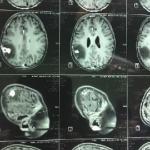

با روش های متعددی توسط آندوسکوپ و میکروسکوپ می توان به قاعده ی جمجمه ی بیماران دسترسی پیدا کرد. بسیاری از اعمال جراحی های سخت امروزه امکان پذیر شده است. به عنوان مثال برای تومور هیپوفیز با استفاده از روش اندوسکوپی از راه سینوس های پارانازال و از راه داخل بینی دسترسی به تومور ورزکسیون آن به سادگی امکان پذیر شده است.

بسیاری از تومور های دیگر قاعده ی جمجمه مثل مننژیومایی که در قاعده ی جمجمه رشد می کند با روش های میکروسکوپی و حتی روش مینیمال انوازیو، از برش های کوچک قابل دسترسی است و بسیاری از این بیماران با این اعمال جراحی به بهبودی کامل می رسند.

امروزه با انواع روش کرانیوتومی یا برداشتن جمجمه و دسترسی به قاعده ی جمجمه و همینطور برداشتن تومور از ناحیه ی کف جمجمه بوسیله ی آندوسکوپ، به بسیاری از این تومور ها دسترسی امکان پذیر شده است.